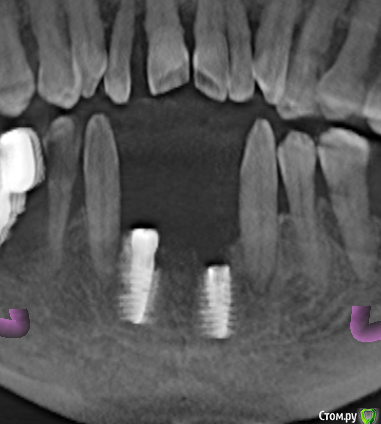

samanta66 Опубликовано 22 марта, 2015 Поделиться Опубликовано 22 марта, 2015 Добрый день.Срочно нужна консультация специалистов. Импланты (передние) поставлены более 9 месяцев назад. Казалось, вросли основательно. На этапе протезирования, когда уже полностью был готов протез, ортопед сказал, что имплант расшатался, послал к хирургу. Сделали снимок, на котором увидели, что имплант стоит не вертикально (как было изначально). 1. Как-то можно исправлять ситуацию? Хирург предлагает убирать этот имплант и через время ставить новый. У меня сомнения: не повторится ли ситуация ?2. Почему имплант расшатался? Во время многочисленных примерок ортопед прилагал немалые усилия, так как что-то там не влезало по моим ощущениям. Можно свидетельствовать, что ортопед своими действиями "свернул" имплант ? Он отказывается переделывать бесплатно свою работу. Для сравнения предлагаю 2 КТ (за октябрь и март). октябрь март крупнее Ссылка на комментарий

diesel87 Опубликовано 22 марта, 2015 Поделиться Опубликовано 22 марта, 2015 стоит судя кт он так же как его и ставили. только видимо нет кости вестибулярно. скорее всего перестановка Ссылка на комментарий